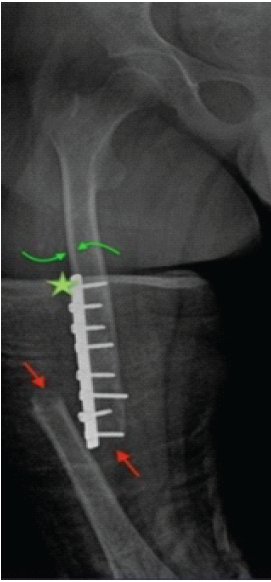

Plain radiographs of the right femur were obtained (Fig. 1), revealing a diaphyseal mid-third fracture with a simple fracture line located immediately distal to the previous osteosynthesis material, cortical thinning was noted without pathological lesions.

Figure 1: Anteroposterior (AP) X-ray of the right femur, February 26, 2025. AP radiograph of the right femur showing a displaced periprosthetic femoral fracture with varus angulation, displacement, and shortening (red arrows). Previous osteosynthesis material is visible without signs of fatigue or loosening (star). Adequate corticomedullary differentiation is observed in the diaphyseal region, along with cortical thinning (green arrows).